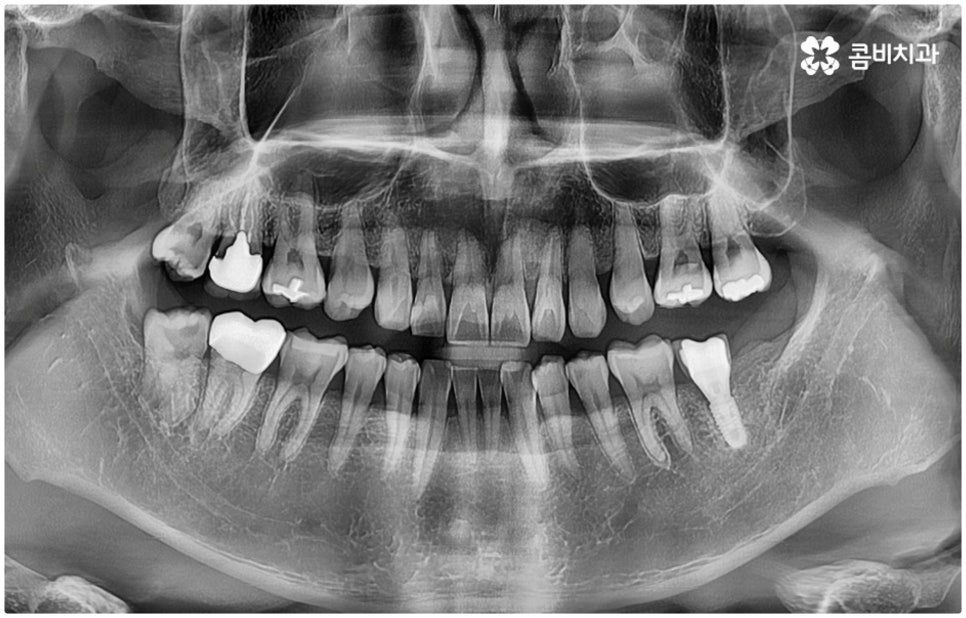

특히 매복 사랑니 중 잇몸 속에 전부 묻혀 있는 사랑니를 완전매복사랑니라고 부르는데 이 경우 누운 방향으로 자라나면서 앞 어금니 뿌리에 지속적인 압박을 가하여 신경을 누르기도 하고 치근을 흡수시키거나 치열이 앞쪽으로 쓰러지게 만들어 부정교합을 유발하기도 하며 드물게는 함치성 낭종이 생겨 턱뼈를 녹이는 상황까지 발생할 수도 있기 때문에 꼼꼼하게 검진을 하여 만약에 필요하다면 늦지 않게 발치 처치를 해 주어야 하는 거예요.

매복사랑니발치치과 를 선택할 때 어떤 것을 기준으로 고르는 것이 좋을까요? 사랑니가 완전히 매복되어 있다면 잇몸을 절개하고 상황에 따라 골삭제 후 치아를 조각내어 빼내줄 필요가 있는데 이러한 과정이 굉장히 까다롭기 때문에 먼저 환자분들의 사랑니 위치 및 뿌리의 형태, 인접 치아 구조, 주변 조직이나 신경 위치 등을 구체적으로 확인할 수 있는 3D CT와 같은 정밀 검진 장비를 갖추고 있는 매복사랑니발치치과 인지 체크해 보실 필요가 있어요.

하악 사랑니의 경우 하치조 신경을 건드리지 않도록 주의해야 하고 상악 사랑니의 경우 상악동 천공을 조심해야 하는데 이 때 환자분들의 상황 또한 개인마다 천차만별인 만큼 각각을 꼼꼼하게 살펴보고 섬세하게 발치 처치를 하기 위해 술자의 뛰어난 기술력 및 숙련도가 요구되므로 매복사랑니발치치과 의료진의 경력 사항을 면밀하게 살펴보시는 것도 도움이 될 거예요.